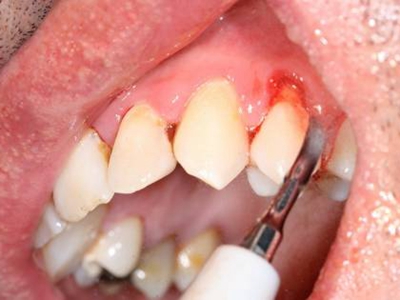

牙龈退缩多处牙龈萎缩出血图

牙龈退缩严重时,上排牙有多颗牙齿的牙龈部位发生退缩,导致牙根暴露,同时牙龈处还有出血的症状,伴有疼痛感,建议及时前往医院通过手术等手段进行治疗。